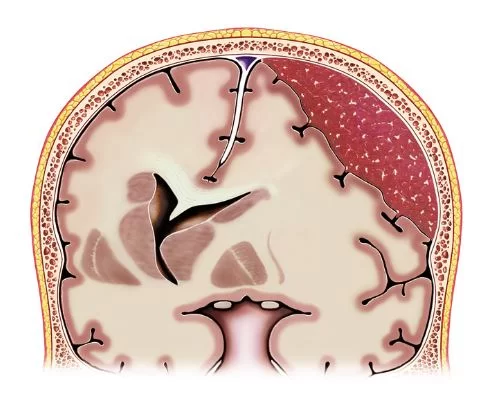

Ανάμεσα στον εγκέφαλο και το κρανίο υπάρχουν 3 περιβλήματα, οι μήνιγγες. Αυτές είναι από έξω προς τα μέσα: η σκληρά, η αραχνοειδής και η χοριοειδής μήνιγγα. Το υποσκληρίδιο αιμάτωμα αθροίζεται (μαζεύεται) ανάμεσα στη σκληρά και την αραχνοειδή μήνιγγα (Εικόνα 1).

Σε αντίθεση, στα επισκληρίδια αιματώματα το αίμα αθροίζεται εκτός της σκληράς μήνιγγας και συγκεκριμένα ανάμεσα στο κρανίο και τη σκληρά μήνιγγα (Εικόνα 2).

Πολύ σημαντικό ρόλο παίζει η αξονική τομογραφία εγκεφάλου (Εικόνα 4). Σε έναν ασθενή με κρανιοεγκεφαλική κάκωση, η αξονική τομογραφία θα δείξει αν υπάρχει υποσκληρίδιο αιμάτωμα ή και κάποια άλλη εγκεφαλική βλάβη, όπως για παράδειγμα εγκεφαλική θλάση, επισκληρίδια ή υπαραχνοειδής αιμορραγία, κάταγμα κ.ο.κ.

Αλλά ακόμα και αν δεν έχει προηγηθεί κάκωση κεφαλής, η αξονική τομογραφία θα βοηθήσει να ελεγξουμε αν υπάρχει χρόνιο υποσκληρίδιο αιμάτωμα ή κάτι άλλο, όπως πχ. κάποιο ισχαιμικό εγκεφαλικό ή εγκεφαλική αιμορραγία. Η μαγνητική τομογραφία δε χρησιμοποιείται τόσο συχνά, έχει όμως πολύ μεγάλη ακρίβεια στο να αναδεικνύει ένα υποσκληρίδιο αιμάτωμα και μπορεί επίσης να αναδείξει και άλλες συνοδές εγκεφαλικές βλάβες.